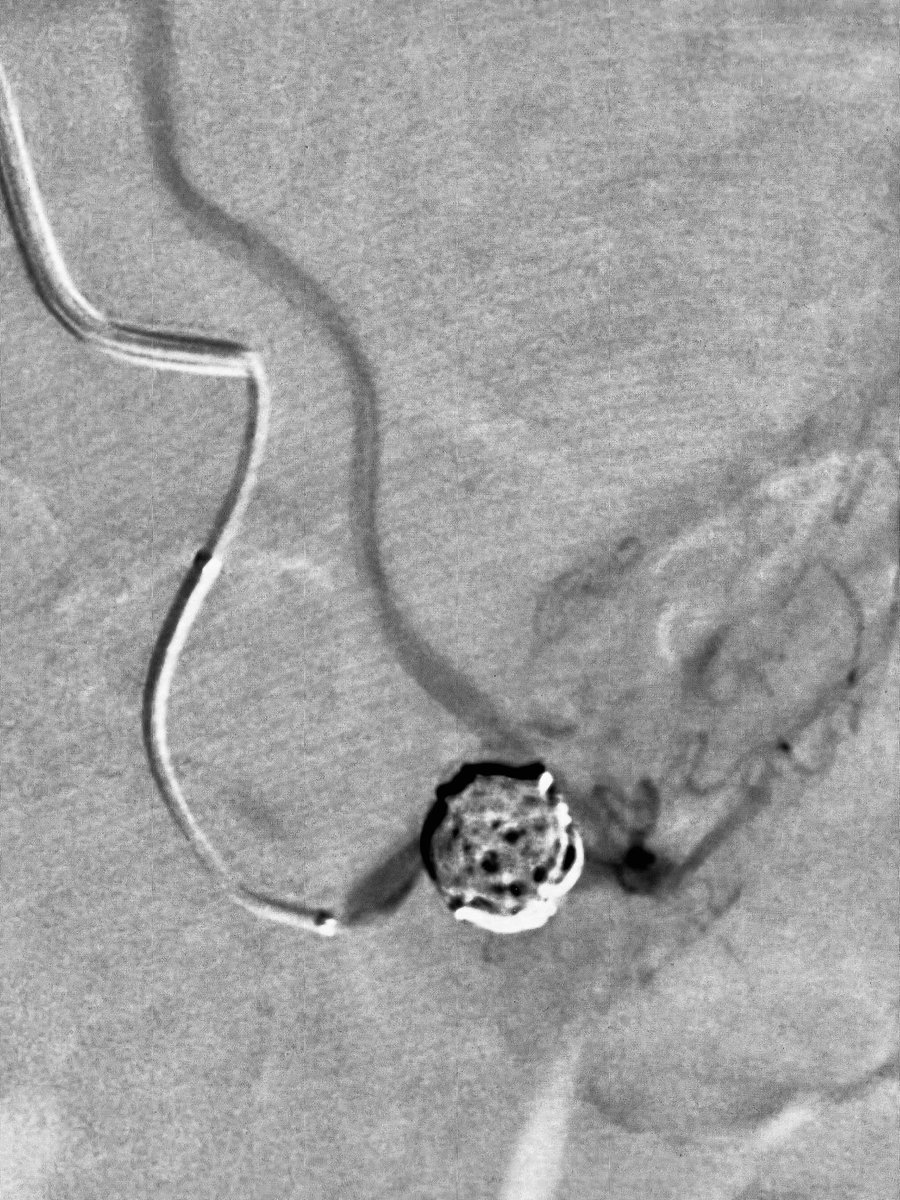

@DrShannonThomas @SIRRFS @SIR_ECS @VA_Int_Oncology @PenVascular Erased the original tweet by mistake. Inflammatory/ruptured SMA branch aneurysm and pain.

@DrShannonThomas @SIRRFS @SIR_ECS Correct! Coiled the aneurysm and the inflow/outflow with Penumbra Ruby, POD and Packing coils. @VA_Int_Oncology @VenuVadlamudiMD @PenVascular